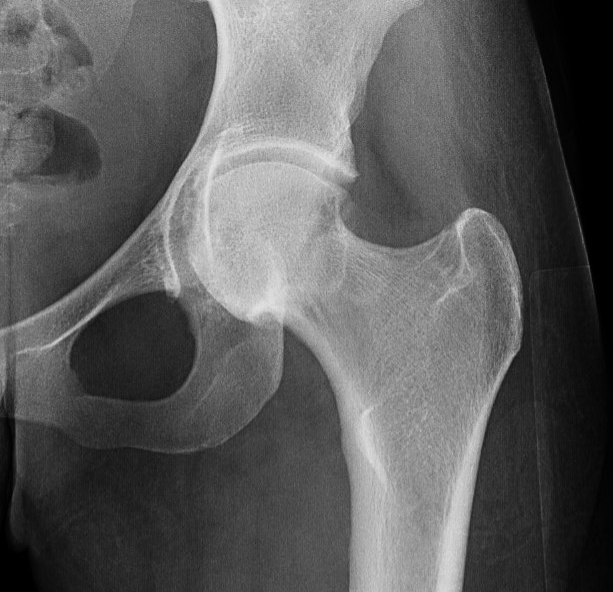

45 and 90 degree Dunn view

Look for Cam morphology

Small Cam on Dunn view Large anterior Cam on Dunn view